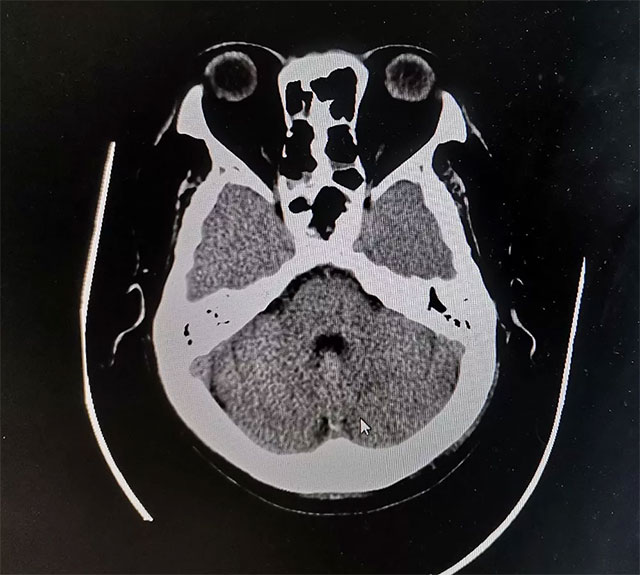

潘仁龙主任指出,CT在垂体卒中急性期平扫时即可见瘤内的高密度影出血灶,很容易辨别,但当进入亚急性期后则呈等密度,难于鉴别。因此,在高度怀疑垂体卒中的病例中应首选MRI扫描。此外,MRI 还能提供较 CT 更为清晰的三维空间解剖结构,它对肿瘤以及瘤体与周边正常组织的关系都可起到良好的显示作用。因此MRI是垂体瘤卒中的首选影像学检查手段,而在急性期,尤其是超急性期则首选CT。